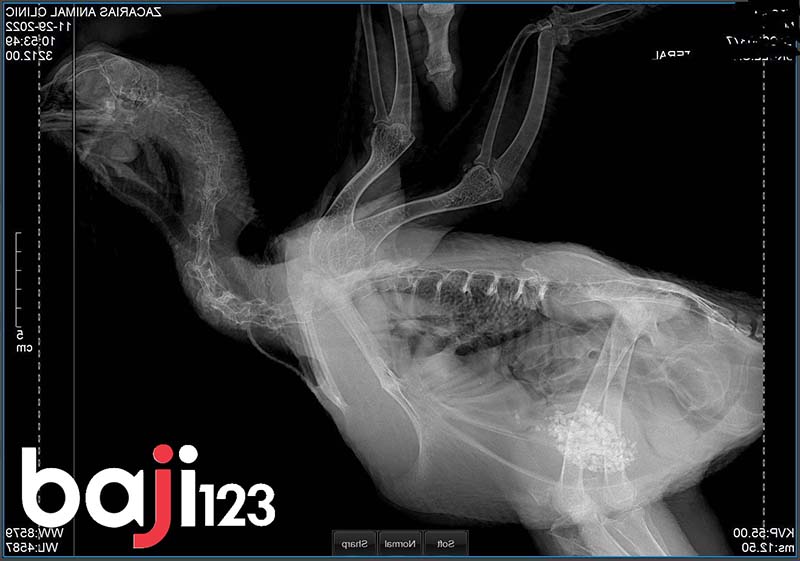

Chụp X quang cho gà

Gãy xương thì phải chụp x quang mới xác định được vết gãy như thế nào và tình trạng chấn thương của chúng ra làm sao. Chính vì lẽ đó chúng ta cần phải đưa chúng tới các cơ sở y tế thú y để xác định các vết thương này như thế nào. Hãy tìm xem cơ sở thú y nào gần nhất để đem tới đó xác định tình trạng chấn thương. Chi phí cũng không quá cao khi chỉ khoảng 50-70k hoặc cùng lắm 100 nghìn mà thôi. Người chụp xquang tay ở phòng khám tư có 50k thì gà chắc cũng tầm đấy. Khi đã có kết quả thì hãy lắng nghe lời khuyên của bác sỹ thú y để biết cách xử lý.